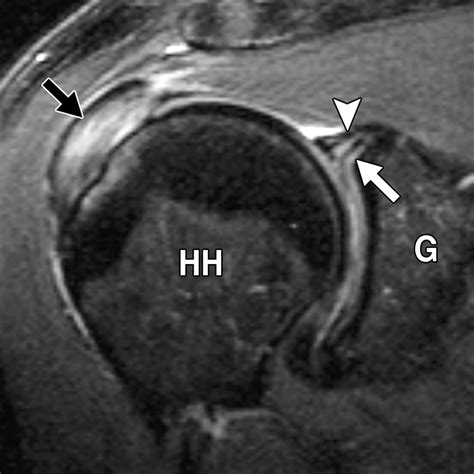

Interpreting the results of a Slap Tear MRI involves a thorough examination of the images by a radiologist. Key findings that indicate a SLAP tear include:

• Abnormal signal intensity within the labrum, suggesting a tear.

• Displacement or detachment of the labrum from the glenoid.

• Fluid or contrast agent extending into the tear, highlighting the extent of the injury.

• Associated injuries, such as rotator cuff tears or biceps tendon pathology.

Radiologists use specific criteria to classify SLAP tears based on their appearance on MRI images. For example, a Type II SLAP tear may show detachment of the labrum and biceps tendon from the glenoid, while a Type IV tear may exhibit a displaced flap of tissue.